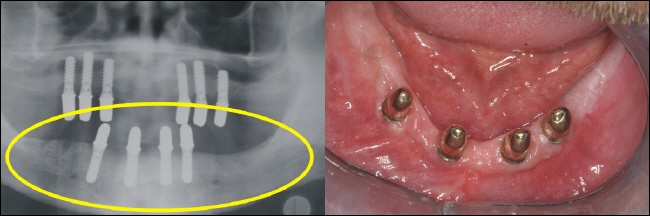

Die fertige Arbeit ermöglicht auf den sechs Teleskopen im Oberkiefer eine rein kieferkammbegrenzte, also gaumenfreie Versorgung. Das Röntgenbild links zeigt die solide Konstruktion, die eine reine Kaukraftweiterleitung in den Kieferknochen ermöglicht. |

Auch im Unterkiefer ist der Zahnersatz auf den Kieferkamm begrenzt und ermöglicht so höchsten Tragekomfort. |